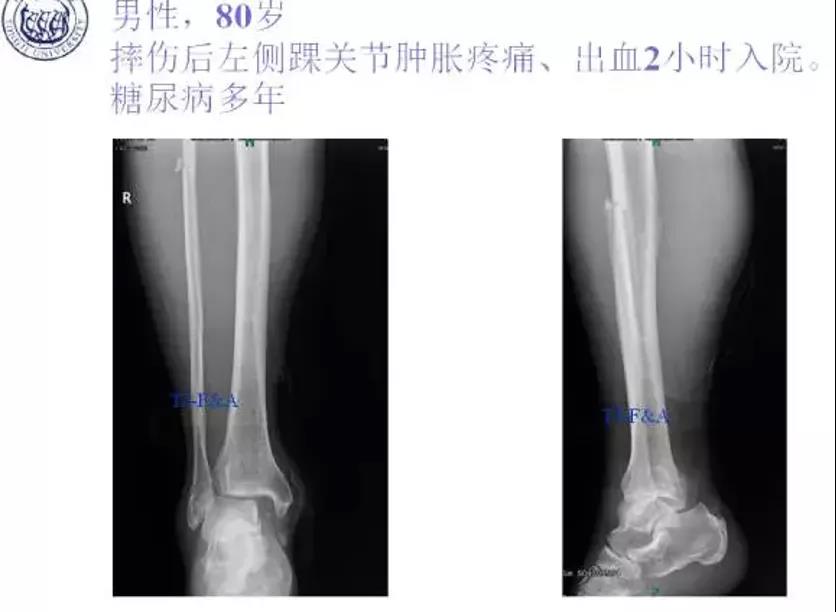

术前

术前DR